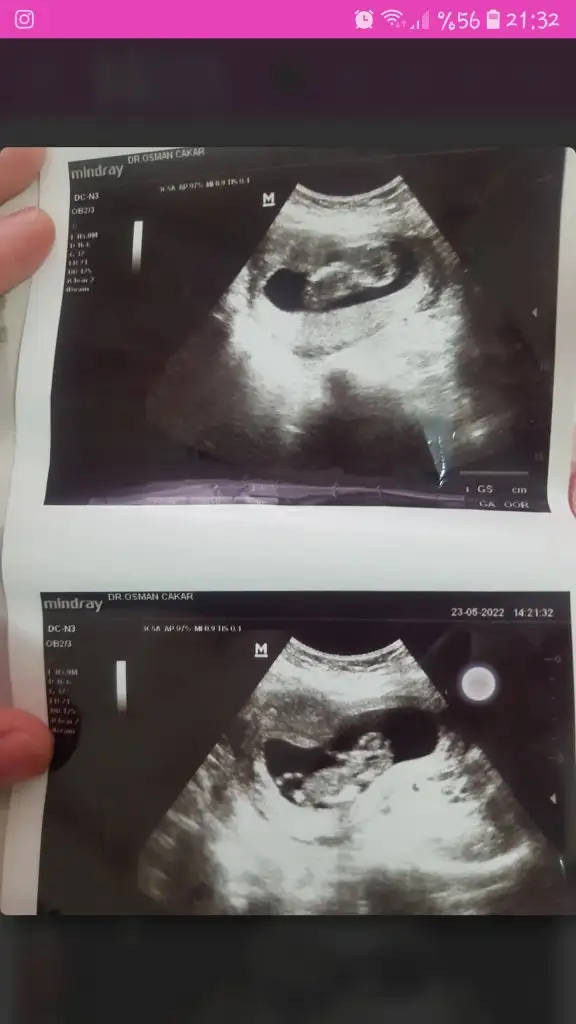

5 ve 14. haftaya kadar olan ultrason fotolarınızı paylaşın. Vajinadan mı yoksa karından mı çekildiğini ve kaç haftalık olduğunu da mutlaka belirtin.

NurSu-14Ocak.!.: tahmin alabilir miyim7+5 karından sizce ne cinsiyeti ?![]()

Ve ayrıca 12 haftalıkken öğrendim ikiz olduğunu size daha önce 6 haftalıkken tahmin yaptınız erkek dediniz diye hatırlıyorumEki Görüntüle 3079866 Slm cinsiyet tahmini yaparmisiniz 12 +2

Ikiz gebelik çift yumurta ikizleri bakalım doğru çıkacakmı 12 de doktor erken dedi 2 hafta sonra randevu 16 haftalık olucam şuan 14